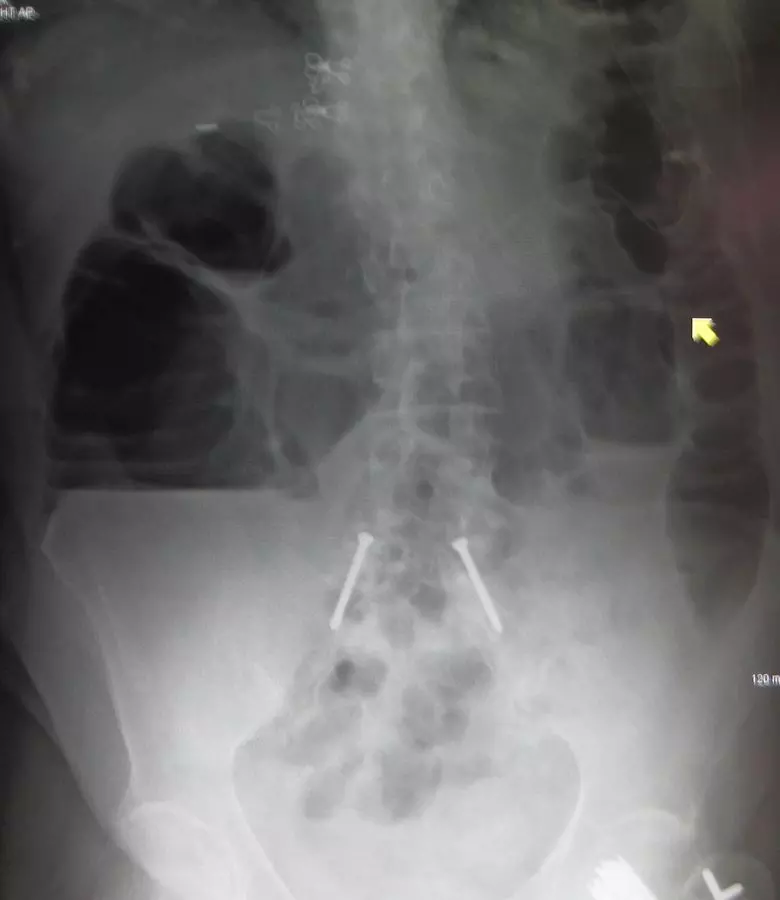

Image - Abdominal x-ray showing large bowel obstruction

Creative commons source by James Heilman, MD [CC BY-SA 4.0 (https://creativecommons.org/licenses/by-sa/4.0)]

First-line diagnostic imaging is a CT scan of the abdomen as it often allows the identification of the location and the cause of the obstruction. The exception to this rule would be if bowel perforation is suspected (e.g. if the pain is disproportionate and unremitting, or the patient is peritonitic), in which case an emergency surgical intervention may be undertaken without a CT scan, or an abdominal x-ray can be taken. Classically, an erect chest x-ray searching for pneumoperitoneum would have been undertaken to check for perforation, but this is performed less often today because it is not reliable. In stable patients, endoscopy can provide a biopsy of a mass causing the obstruction and can be both diagnostic and therapeutic if sigmoid volvulus is the cause of the obstruction.

Large bowel obstruction is considered a gastrointestinal emergency because of the high risk of complications such as dehydration/metabolic alkalosis, sepsis, bowel ischaemia/necrosis and perforation.

Most cases are managed surgically.